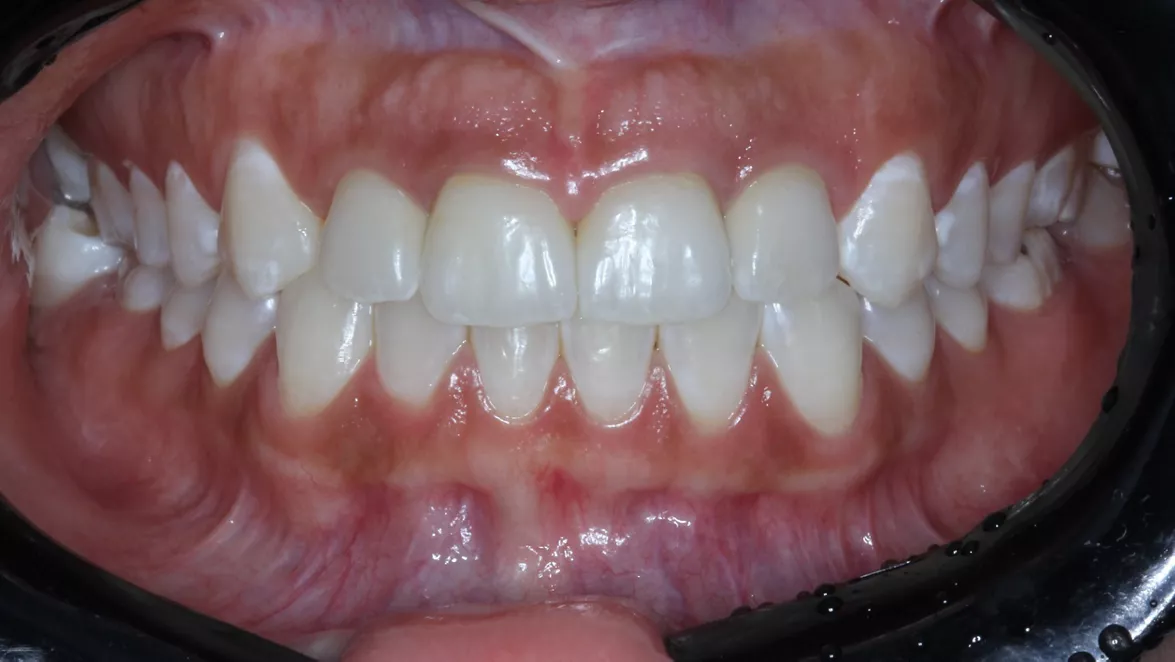

23 - Immediate aesthetic rehabilitation with Neodent® Zi Ceramic Implant System

Dr. Ricardo Kern